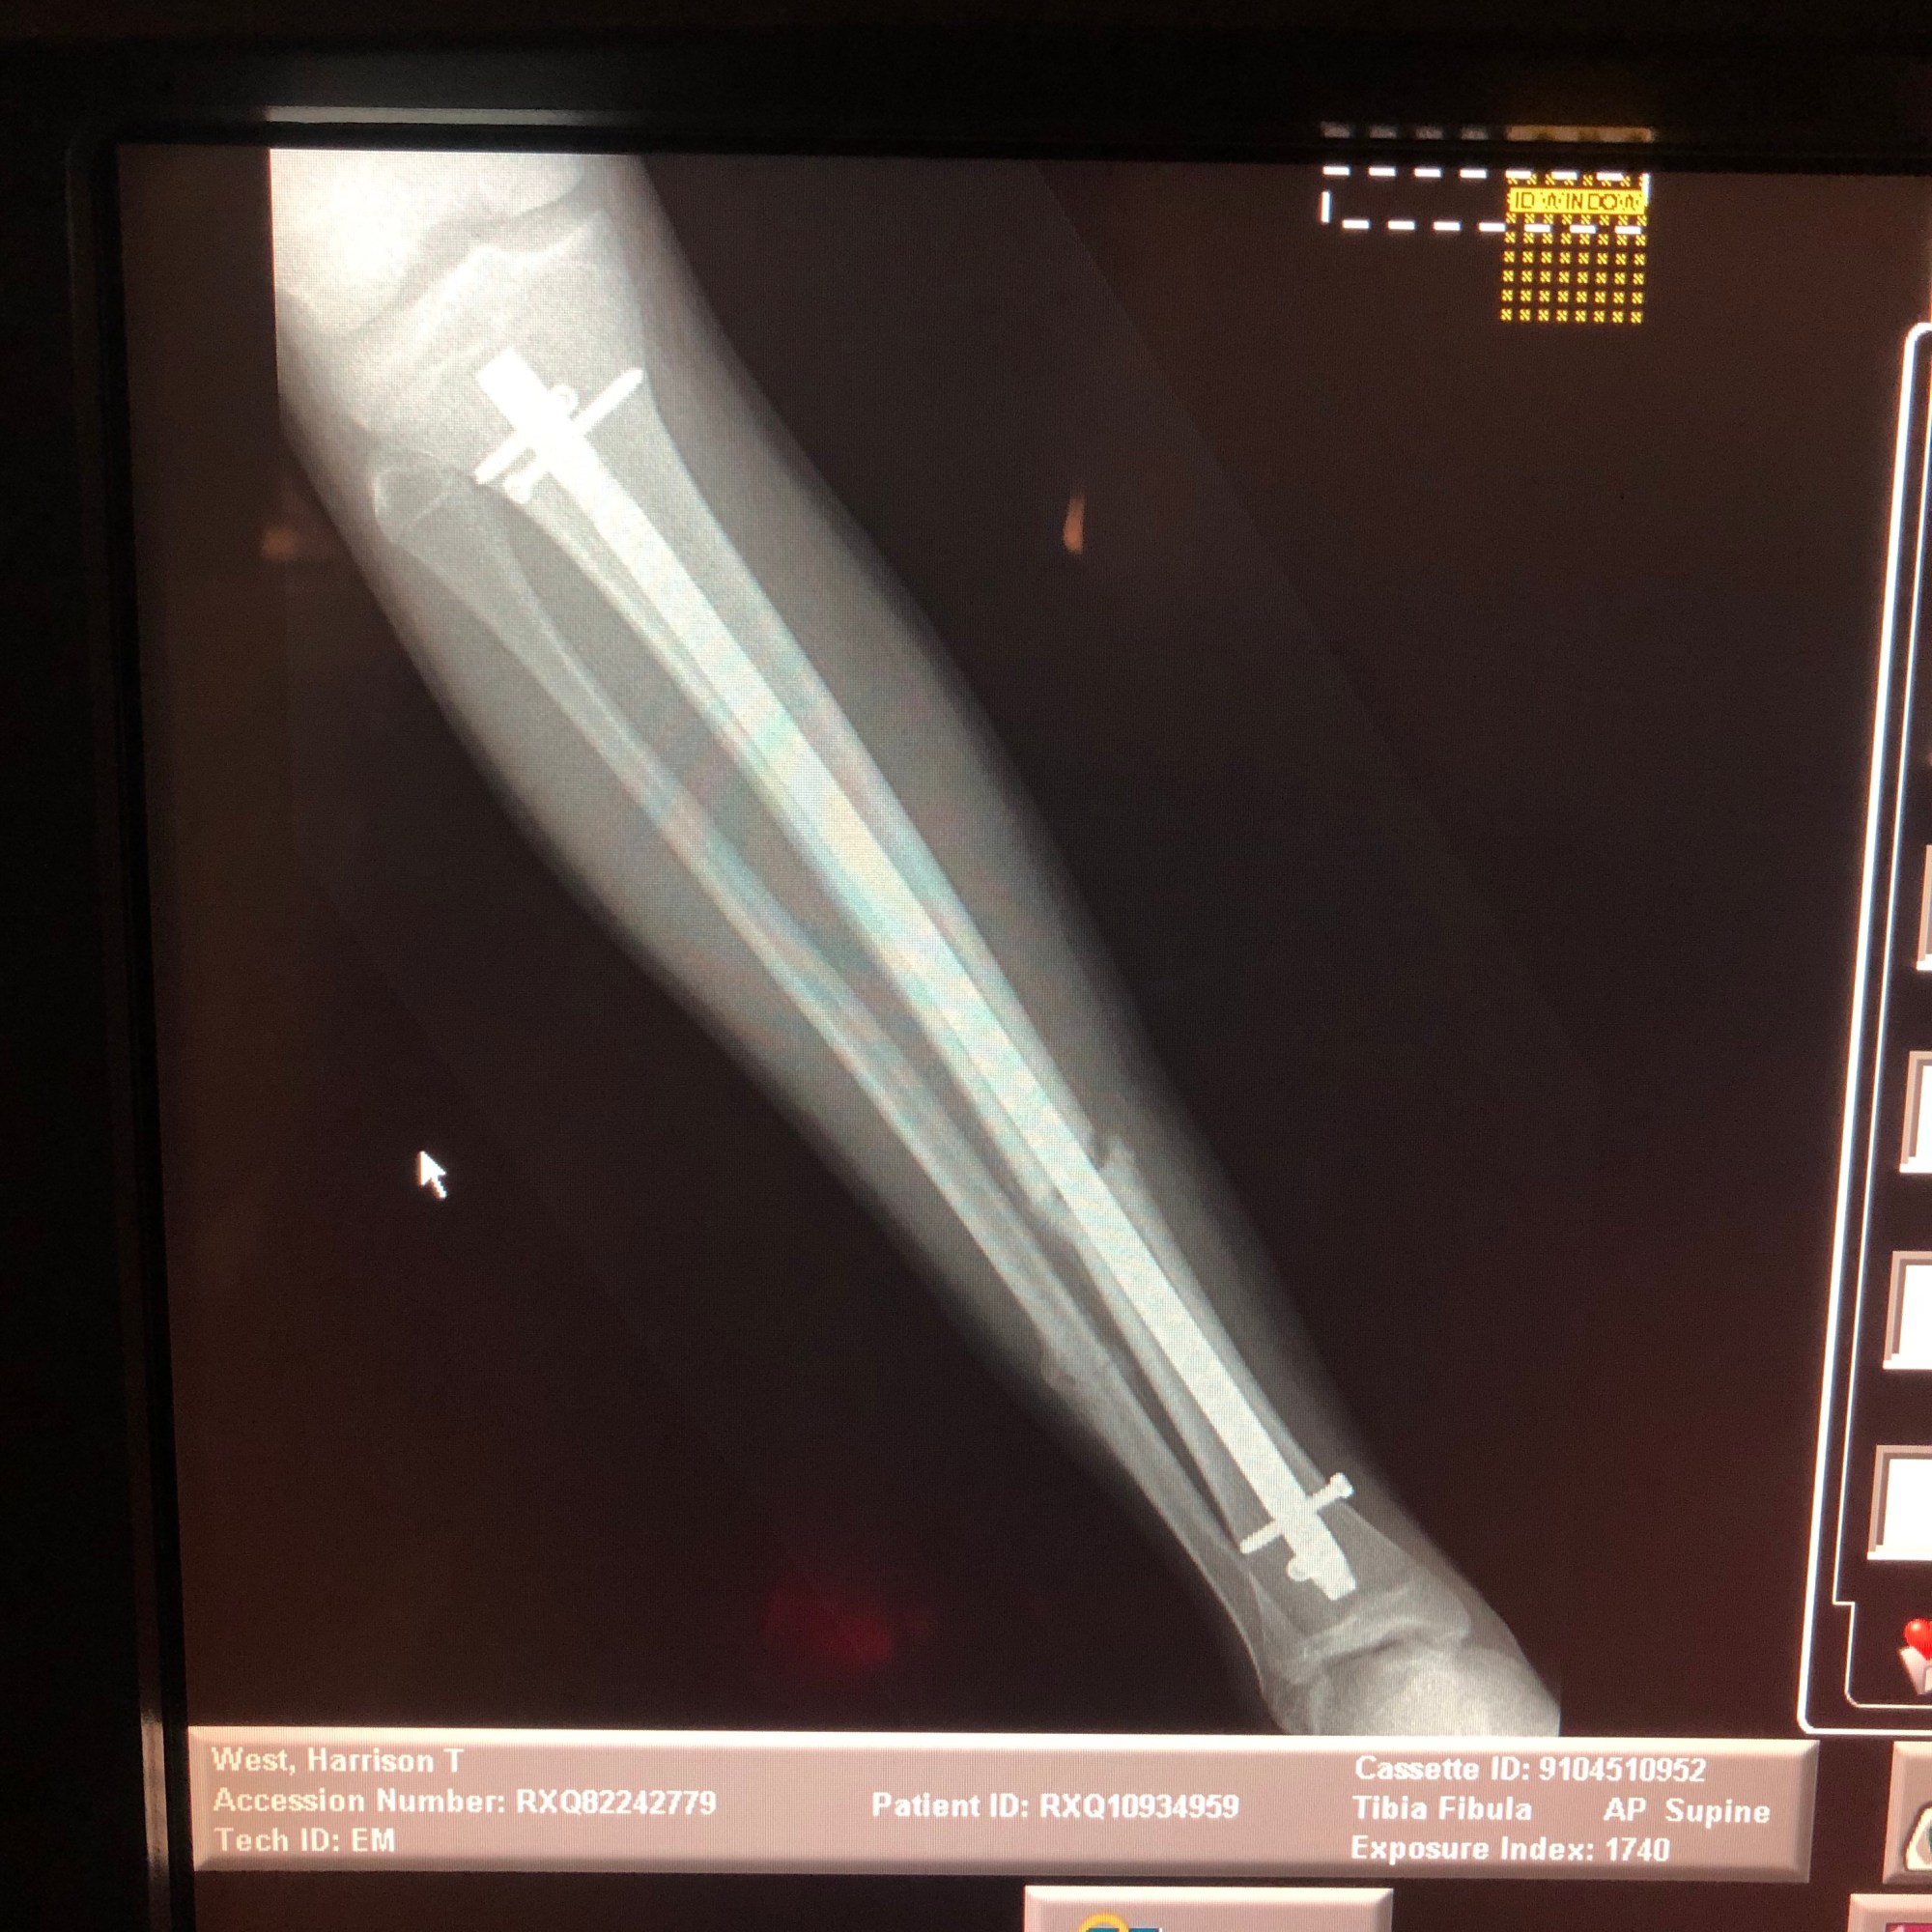

On a personal note this year has been brought much drama, We have had 3 broken bones, a collarbone in August and both Fibula and Tibia broken in November resulting in surgery with a nail inserted through H’s right leg. The road to full recovery will be long, both physically and mentally but ‘H’ is one tough cookie and I have witnessed an inner steel in him that will stand him in great stead for the future, literally !